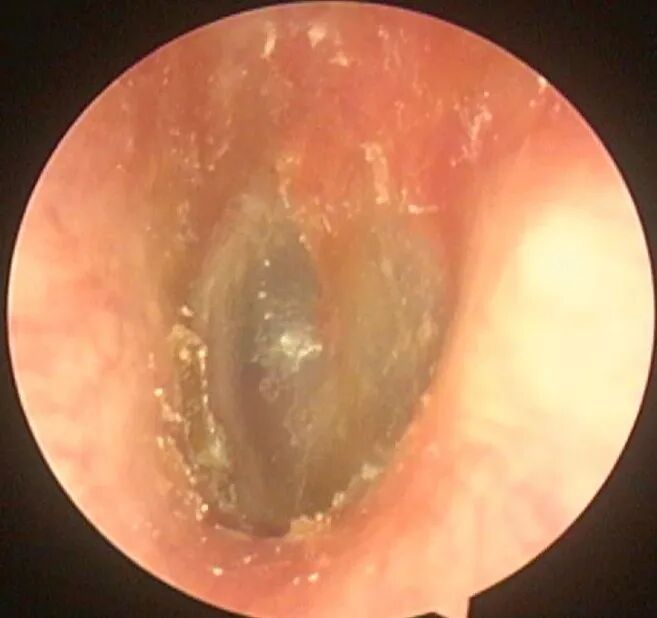

像这样的: